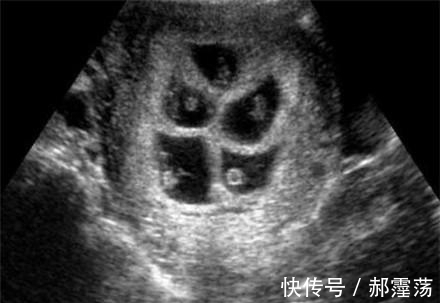

家里人吓的赶紧带孕妈去医院检查,没想到却听到一个令人振奋的消息,原来孕妈肚子这样的大,居然是因为肚子里不只怀了1个孩子,而是5胞胎。

杨女士和丈夫结婚1年后发现自己怀孕了,全家人都高兴不已,特别是丈夫,因为他现在已经40岁了,要想他这样的年龄朋友的孩子都可以买酱油了。然而杨女士怀孕两个月的时候肚子大的出奇,实在放心不下,丈夫就带着杨女士到医院检查,检查发现原来检查结果出来了杨女士夫妻俩人是即高兴又担心,高兴的是医生说杨女士怀了四胞胎,担心的是杨女士的身体,这才两个月肚子就这么大了,要是再晚几个月可想而知。

医生说为了安全建议减胎,于是杨女士夫妻俩商量了一下,决定减胎。到了医院在做减胎手术前的检查时,医生的一句话又让她们犹豫了,说是五胞胎,要减三个,但是减三个的话手术危险挺大的,可能会导致胎儿流产,或终生不育,两人瞬间不知道怎么办了。